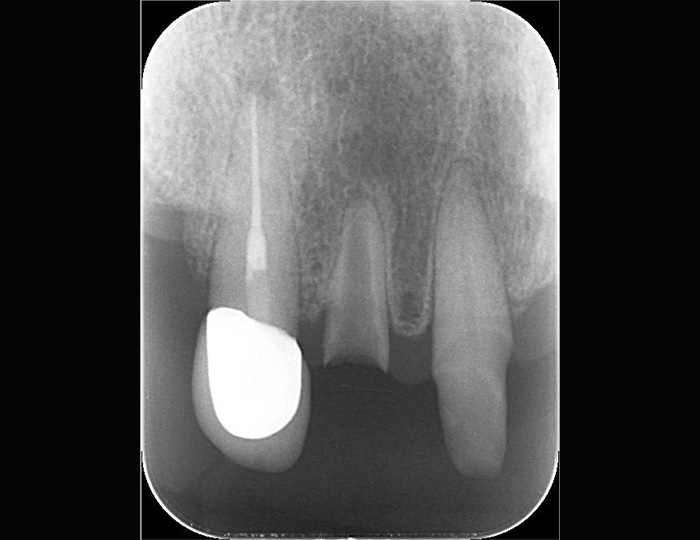

| 主訴 | 右上の被せ物の色が気になる。 固いものを噛むと響く。 |

| 治療内容 | 前装金属冠を除去後、マイクロスコープ下にてサージカルバーと エンドチップを用いてメタルコアを除去。 手用ファイルにて穿通後、感染歯質を除去して根管充填。 |

| 主訴 | 奥歯で固いものを噛むと響く |

| 治療内容 | マイクロスコープ下にて感染歯質除去時に破折器具を発見。 エンドチップを用いて破折器具を除去。 |